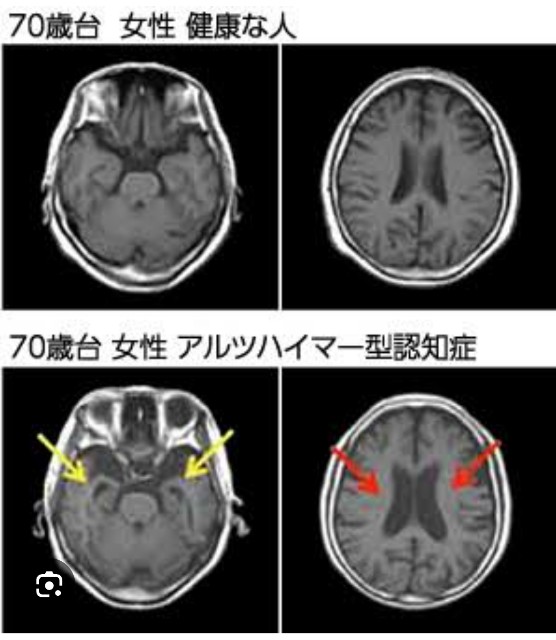

器質(脳の変化)→内因(統合失調症躁うつ病等)→心因(ストレス・心理的負担等)

精神科医はこの順番で除外し診断 各々に沿った治療・場合によっては紹介を進めるのが原則 が心因・ストレスから精神的不調を説明しようとされる事が多いのが現実